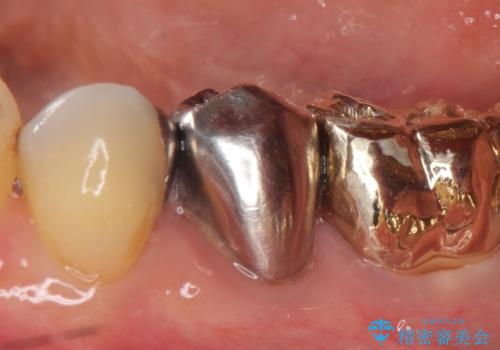

- 左下5番目の歯を根管治療からやり直したいといらっしゃった方の症例です。

再根管治療終了後、オールセラミッククラウンによる補綴を行いました。

- オールセラミッククラウン…¥100,000、仮歯…¥10,000、ファイバーコア…¥20,000費用は治療当時の料金となります